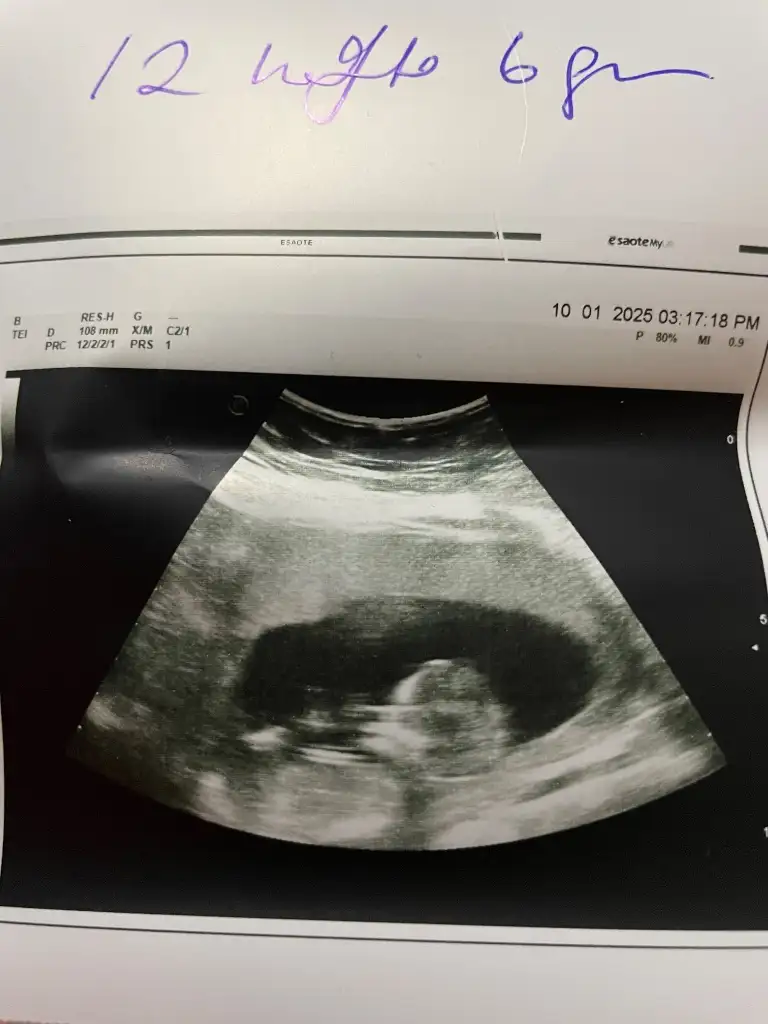

Çok net görünüyor erkek. Hayırlı olsunMerhabalar 12+5 haftalik hamileyim doktorum bugun cinsiyeti söyledi ama bana biraz erken gibi geliyor. Görsellerden tahmin edebilcek var mı acaba. Doktorum bakarken sürekli göbek kordonu bacak arasında dedigi icin emin olamadım. Doktorumun demesine göre oglum olcakEki Görüntüle 3528053

Direk çıkıntı var bence hayırlı olsun şimdidenMerhabalar 12+5 haftalik hamileyim doktorum bugun cinsiyeti söyledi ama bana biraz erken gibi geliyor. Görsellerden tahmin edebilcek var mı acaba. Doktorum bakarken sürekli göbek kordonu bacak arasında dedigi icin emin olamadım. Doktorumun demesine göre oglum olcakEki Görüntüle 3528053